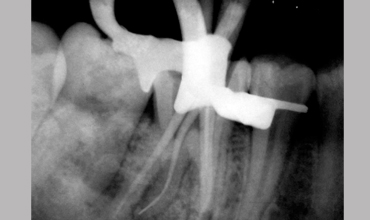

Management Of Radix Entomolaris In Mandibular First Molar